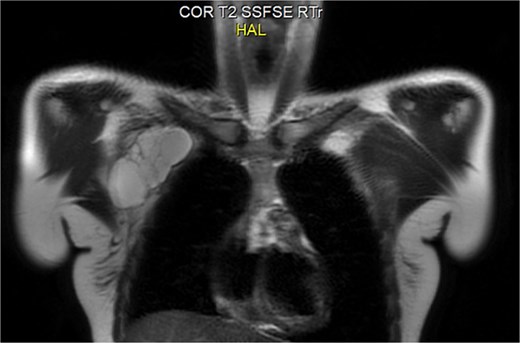

A 20-year-old previously healthy woman presented with a progressively enlarging, painless mass in the right chest wall extending into the axilla, associated with right arm heaviness, stiffness, and intermittent fatigue. She had a history of right cheek masses excised at ages 8 and 17, both histologically diagnosed as lymphangiomas. Examination revealed a large, soft, fluctuant, non-tender mass in the right axillary and lateral chest wall regions. MRI showed an 11.0 × 8.5 × 4.5 cm multiloculated cystic lesion with T2 hyperintensity and compression of the right axillary and subclavian veins (Figs 1 and 2). A diagnosis of recurrent cystic lymphangioma was established, and she underwent complete surgical excision with careful dissection to avoid neurovascular injury and management of lymphatic channels to reduce postoperative lymphocele formation. Postoperatively, her upper limb symptoms resolved, and she regained normal function. Given a recurrence risk of 10%–27% even with total excision, regular follow-up imaging was planned. This case underscores the need to consider lymphangiomas in adults with cystic masses, highlights the embryological explanation for ipsilateral recurrences along the cervicoaxillary pathway, and emphasizes the importance of MRI and computed tomography (CT) in diagnosis and surgical planning.

While cervical lymphangiomas dominate pediatric presentations, adult-onset axillary and chest wall lymphangiomas are exceptionally rare [2, 3]. Symptoms often manifest only after significant enlargement causes mass effect on neurovascular structures, as seen in our patient’s arm weakness and heaviness. MRI is the modality of choice, demonstrating characteristic T2 hyperintensity and thin septations; CT adds value in delineating relationships with critical neurovascular structures for surgical planning [3, 4].